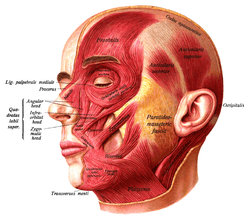

Muscles of the head, face, and neck. (Nasalis labeled at center left.) | |

Position of nasalis muscle (shown in red).